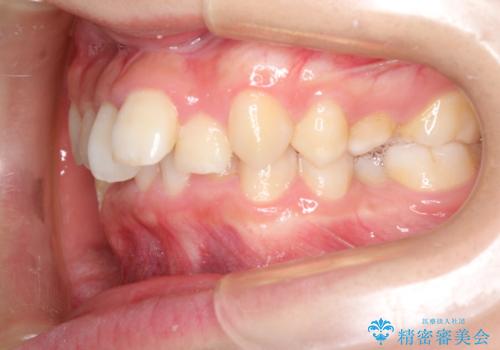

重度のガタガタのインビザラインによる非抜歯矯正

- 全体的なガタガタを気にされて来院されました。

抜歯矯正も考えられる状態でしたが、ご本人的になるべく歯を抜かない矯正を希望されました。

奥歯を後方に移動させるのと、歯と歯の間にわずかに隙間を作ることでスペースを確保して、抜歯をせず歯を並べる計画としました。

ガタガタの度合いが大きかったので少し時間がかかりましたが、非常に協力的な患者様でしたので、抜歯をせず計画通りに治療を終えることができました。